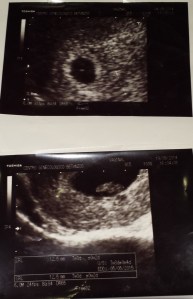

Sinceramente a mí me encanta ser mamá, me encantan los niños y estar embarazada, me fascina comprobar una y otra vez la vida que se gesta dentro de mí, sentir sus movimientos y después de unos meses maravillosos ver salir una personita de mí, como pasa de ser tan indefenso y dependiente a tener su propia personalidad y brillar por ser tan único e irrepetible, observar cómo crecen, aprenden todo…

Además, también creo que con cada embarazo intento reparar lo que ocurrió en el primero, (pérdida de mellizos en la semana 20) ya que desde ahí dijimos que los bebés que quieran venir serían bienvenidos…